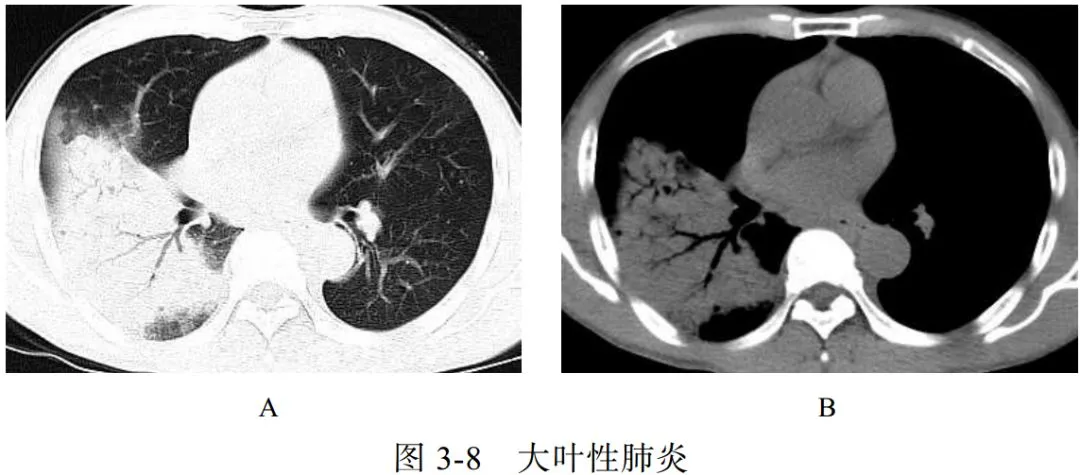

(一)大叶性肺炎

大叶性肺炎以秋冬季节多见,常见于青壮年,致病菌主要为肺炎链球菌、肺炎克雷伯菌、军团菌,常累及整个肺叶或肺段。临床表现为突然发病、畏寒发热、胸痛、咳嗽、咳痰,白细胞和中性粒细胞计数明显升高等

影像学表现:

(1)充血期肺组织呈边缘不清的云雾状影,实变期呈大片实变影(图 3-8A)、充气支气管征(图 3-8B),消散期呈散在斑片状影

(2)肺炎链球菌肺炎与肺炎克雷伯菌肺炎的区别:前者支气管充气征清晰可见,可达胸膜下;后者因分泌物黏稠,支气管充气征显示不佳

(3)溶血链球菌肺炎容易出现空洞